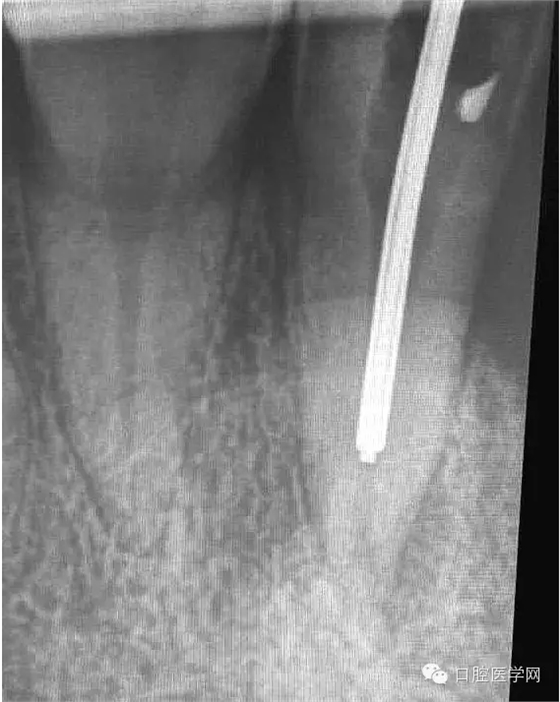

患牙有嚴(yán)重叩診不適。根尖片明確的顯示了牙根根尖喇叭口及根尖均有低密度影像。2年前有外傷史,右上側(cè)切牙缺失。

4.準(zhǔn)備放置橡皮障(由于拍片是較遠(yuǎn),所以,橡皮章暫時(shí)取下),去除暫封材料。在顯微鏡放大視野中,蔣調(diào)拌好MTA輸送至根尖部。